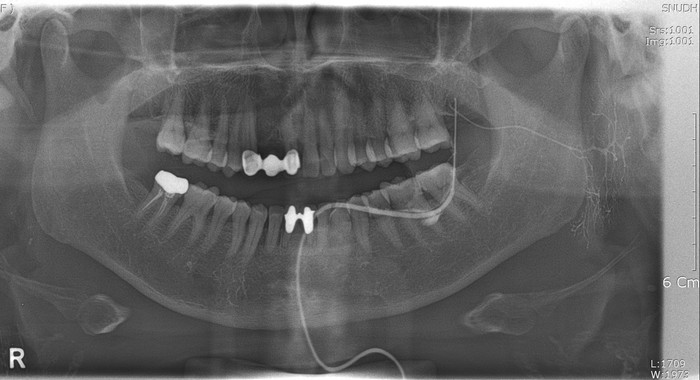

이하선조영술 영상 (예시)

1. 타액선 내에 조영제를 주입하기 위해 개구공의 위치를 파악한다 - 이하선 조영술(Parotid gland Sialography) : 뺨 안쪽에 개구부 위치. - 악하선 조영술(Submandibular gland Sialography) : 혀 하방에 개구부 위치 2. 개구공 확인 후 탐침으로 도관을 찾는다. 3. 개구공이 적절한 크기로 확장되면, 타액선 조영술용 카뉼라(cannula)를 도관 내에 삽입한다 4. 카뉼라를 통해 조영제를 서서히 주입 5. 주입된 조영제를 검사하기 위하여 파노라마 촬영(Panoramic radiography)과 전후방향 촬영(A-P projection) 및 하악지촬영(Mandibular ramus projection)을 시행한다. 6. 일정 시간이 지난 후 파노라마 촬영을 실시하여 조영제가 타액선 내에 남아 있지는 않는지 확인한다.

방사선 사진을 찍은 직후 전문가의 판독을 통해 결과를 바로 확인 할 수 있다. 타액선조양상에서 도관계의 변위나 단절 등의 간접적인 소견으로 종괴 유무를 알 수 있으나 그 크기가 1cm 이상이 되어야 관찰이 가능하며, 타액선 내 종괴와 타액선 외 종괴의 구별이나 양성과 악성의 구별이 어려운 경우가 많아 종괴가 의심될 경우에는 초음파검사, CT, MRI 등의 추가검사를 시행한다.